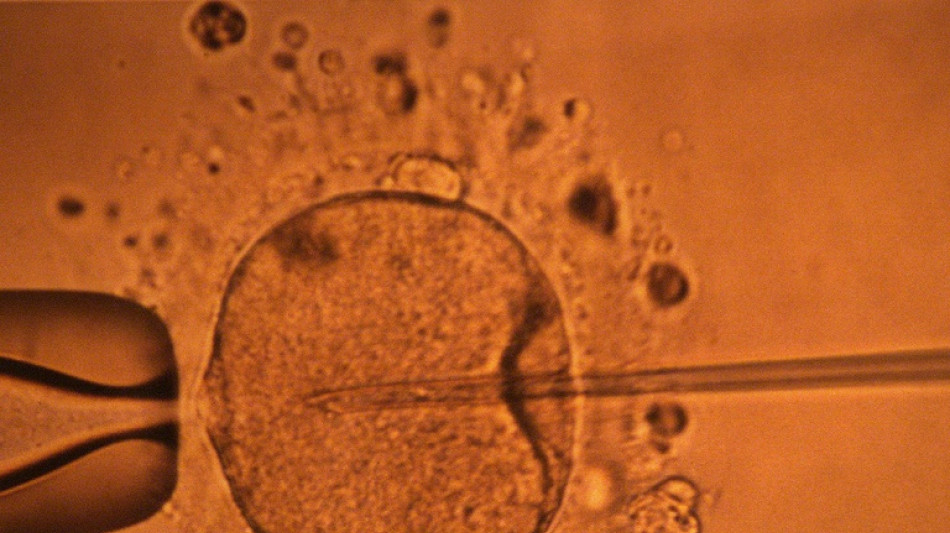

Un estudio apoya hipótesis de disminución mundial de concentración de espermatozoides / Foto: MARCEL MOCHET - AFP/Archivos

La concentración de espermatozoides, uno de los factores de la fertilidad masculina, disminuyó significativamente en todo el planeta en las últimas décadas, según un estudio publicado el martes.